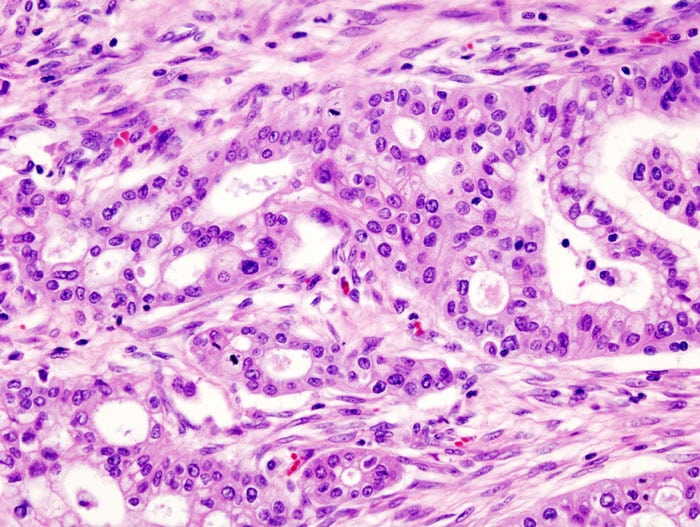

Cette étude promue par Unicancer évalue les effets d’une nouvelle chimiothérapie de précaution (« adjuvante ») chez des patients opérés d’un adénocarcinome canalaire du pancréas, la forme la plus fréquente de cancer du pancréas. Il s’agit d’une étude internationale, de phase III, multicentrique et comparative conduite en France et au Canada avec la collaboration du Groupe canadien des essais sur le cancer (CCTG), financée en France par le Ministère de la Santé et par la Ligue nationale contre le cancer.

L’agence Santé publique France (anciennement Institut de Veille Sanitaire) a estimé en 2015 à environ 11 300 le nombre de nouveaux cas annuels de cancer du pancréas en France. Parmi les cancers du pancréas exocrine, l’adénocarcinome canalaire pancréatique représente 90 à 95 % des formes de ce cancer. La grande majorité des personnes diagnostiquées a plus de 60 ans. Le diagnostic est le plus souvent réalisé à un stade avancé du fait d’une expression clinique tardive de la maladie. Seuls 15% à 20% des patients sont diagnostiqués à un stade où la tumeur est résécable et, lorsqu’elle est possible, la chirurgie est le traitement principal du cancer du pancréas.